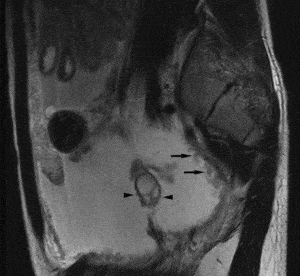

Из первичного очага при снижении иммунной резистентности организма из-за хронических инфекций, стрессов , микобактерии попадают в половые органы. Инфекция распространяется в основном гематогенным путем, чаще при первичной диссеминации в детстве или в периоде полового созревания. При туберкулезном поражении брюшины возбудитель попадает на маточные трубы лимфогенно или контактным путем. Прямое заражение при половых контактах с больным генитальным туберкулезом, возможно только в теории, этому препятствует многослойный плоский эпителий вульвы, влагалища и влагалищной порции шейки матки, который устойчив к микобактериям. Наиболее подвержены заражению маточные трубы (90-100%). Второе место занимает эндометрий (25- 30%). Реже встречается туберкулез яичников (6-10%) и шейки матки (1-6%), крайне редко - туберкулез влагалища и наружных половых органов. В очагах поражения происходят типичные для туберкулеза морфогистологические изменения: экссудация и пролиферация тканевых элементов, казеозные некрозы. Туберкулез маточных труб часто заканчивается их облитерацией, экссудативно-пролиферативные процессы могут привести к образованию пиосальпинкса, а при вовлечении в специфический пролиферативный процесс мышечного слоя маточных труб в нем образуются туберкулы, это называют нодозным воспалением. При туберкулезном эндометрите так же выражены продуктивные изменения - туберкулезные бугорки, казеозные некрозы отдельных участков. Туберкулез придатков матки часто сопровождается вовлечением в процесс брюшины с асцитом, петель кишечника с образованием спаек, а в некоторых случаях и фистул. Генитальный туберкулез часто сочетается с поражением мочевых путей.